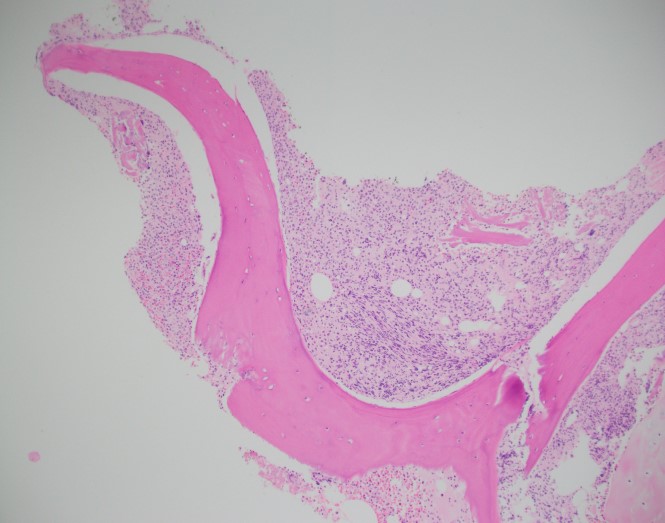

A 23 year old man presented to the hospital with recurrent fever up to 103F with associated nausea and vomiting, epistaxis, watery diarrhea, dyspnea, and decreased appetite for several days. Blood cultures from admission were positive for MSSA and a stool PCR was positive for Vibrio species. He was admitted and treated for sepsis. His CBC demonstrated a marked pancytopenia ( WBC count 0.6 K/μL) and the hematopathology team was consulted to review the peripheral blood film.

Review of the peripheral blood confirmed a markedly pancytopenic picture with virtually no leukocytes in the region of best RBC “spread” (Image 1A). In the periphery of the smear (1B and C) clusters of leukocytes were noted where left-shifted granulocytes were seen. Many demonstrated nuclear irregularity and abnormal granulation (B) and some showed the presence of numerous Auer rods (Image 1C, arrows).

The presence of abnormally granulated immature neutrophilic precursors, and cells with numerous Auer rods was morphologically compatible with acute promyelocytic leukemia (APL) and a rush preliminary diagnosis was rendered. The patient was started on ATRA therapy and FISH for PML-RARA was expedited.

Two distinct subtypes of APL exist: hypergranular (typical) or microgranular. The hypergranular variant is filled with large Auer rods and with dense cytoplasmic granules that can obstruct the nucleus. In contrast, the microgranular variant has a scantiness of cytoplasmic granules or small azurophilic granules.